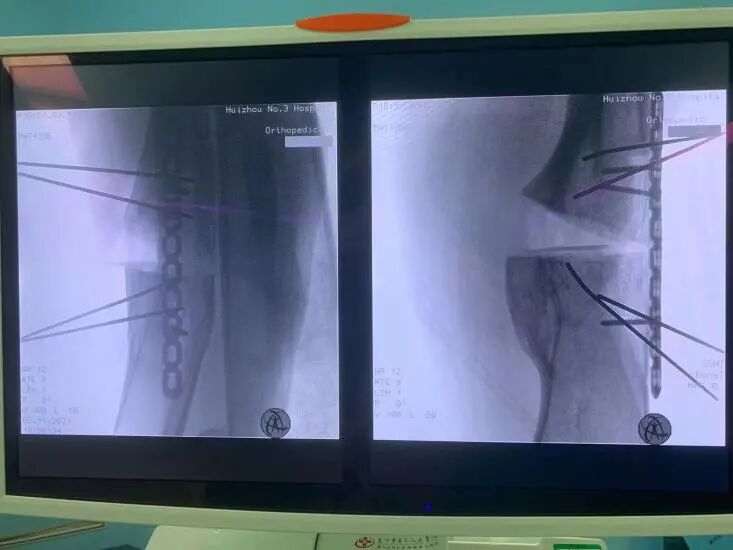

術(shù)中截骨后影像

術(shù)中鋼板螺釘固定后影像